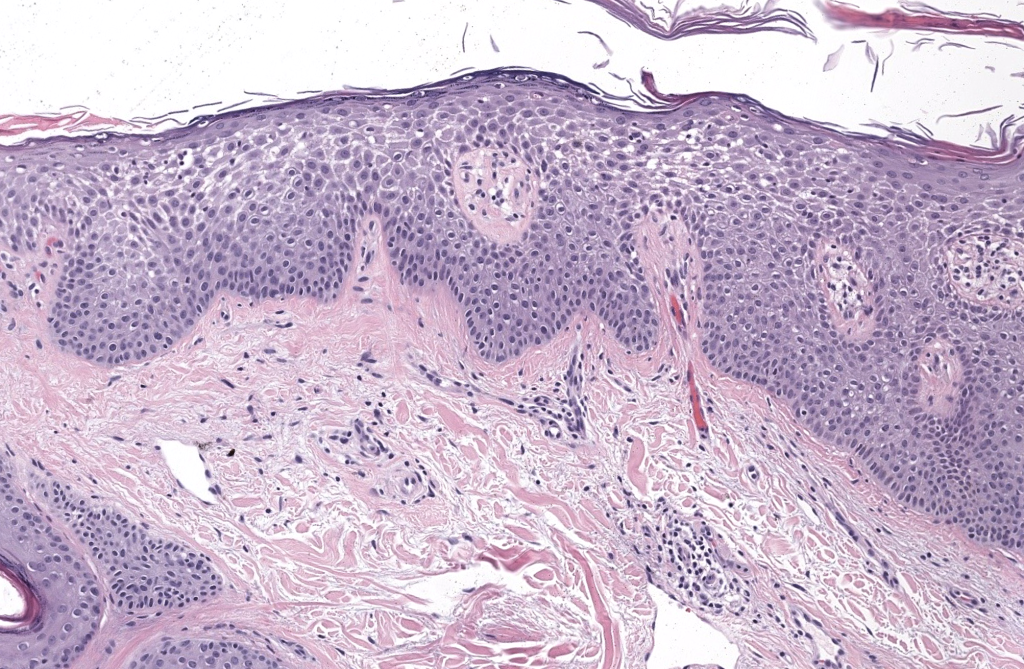

- Nombres/alias: dermatitis atópica, eczema atópico; “prurigo de Besnier” como precursor histórico. PubMed+1

- Primera descripción: el término “atopic dermatitis” fue acuñado por Wise y Sulzberger en 1933. Precursores: prurigo de Hebra/Besnier. PubMed+2PubMed+2